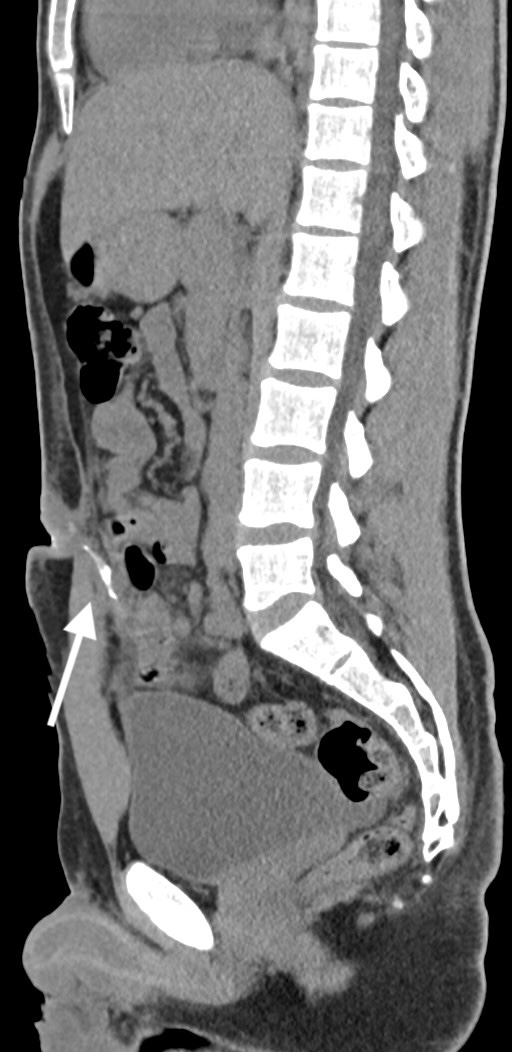

Three years after the appendectomy, the patient returned to the emergency department due to periumbilical pain and erythema that had persisted for three months. On further questioning the patient also reported intermittent diarrhea for one week, with no accompanying vomit or fever. During the physical examination, erythema and pain upon palpation of the umbilicus were observed. The blood tests showed no significant changes. Imaging with a CT scan and fistulogram through the umbilical granuloma allowed for the identification of a fistulous tract to a pericecal collection (figure 1-3). The patient was admitted and started on empiric antibiotic therapy with piperacillin and tazobactam.

Fig. 3: CT scan with fistulogram through the umbilical granuloma showing the fistulous tract to the cecum (white arrow) - sagital view.